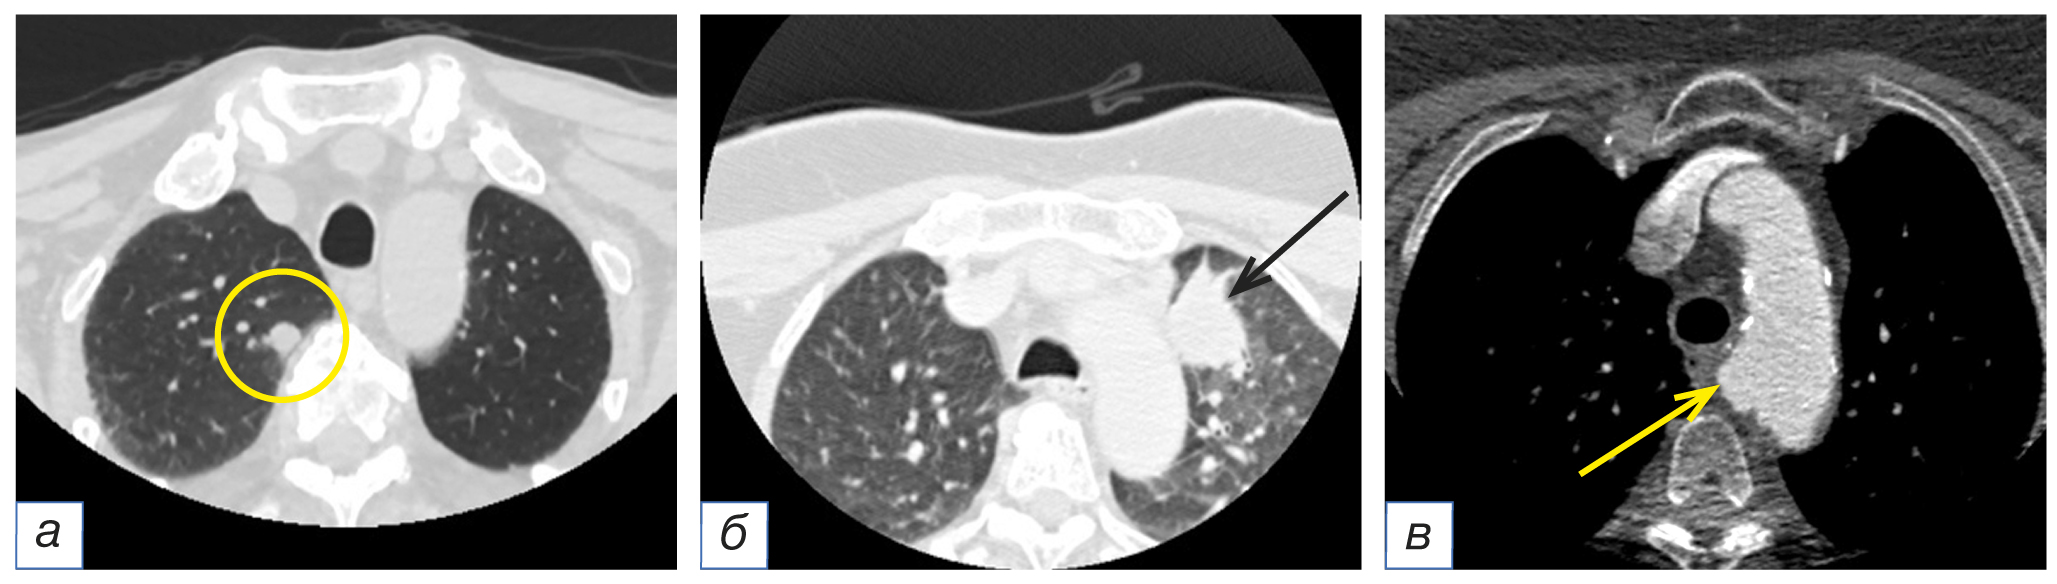

На нижней границе исследования в зоне сканирования ретроспективно визуализировались изменения в лёгочной ткани (n=5; 8,1%) и средостении (n=4; 6,5%). В лёгких определялись признаки очаговых изменений, характерных для метастатического поражения (n=3) или периферического рака (n=2), в то время как в средостении отмечались увеличенные внутригрудные лимфоузлы (n=3) и признаки аневризмы дуги аорты (n=1) (рис. 4).

Рис. 4. Фрагменты компьютерных томограмм области головы и шеи в аксиальной плоскости (а–в). У пациентки в возрасте 71 года с диагнозом базально-клеточного рака кожи шеи слева сТ1N0M0 в верхней доле правого лёгкого определяется одиночный солидный очаг округлой формы с чёткими ровными контурами мягкотканной плотности диаметром 12 мм (а, жёлтый круг). У пациентки в возрасте 68 лет с подозрением на рак левой половины гортани в верхней доле левого лёгкого визуализируется периферическое образование мягкотканной плотности с чёткими неровными контурами размером 37×28 мм (б, чёрная стрелка). У пациентки в возрасте 79 лет с подозрением на рак левой половины гортани определяется мешотчатое расширение дуги аорты по верхневнутренней её поверхности (в, жёлтая стрелка).

Fig. 4. Computed tomograms of the head and neck, axial planes (а–в). In a 71-year-old patient with basal cell skin cancer on the left side of the neck cT1N0M0, a single solid round-shaped lesion with clear, even contours of soft tissue density with a diameter of 12 mm is identified in the upper lobe of the right lung (а, yellow circle). In a 68-year-old patient with suspected cancer of the left half of the larynx, a peripheral formation of soft tissue density with clear uneven contours measuring 37×28 mm is visualized in the upper lobe of the left lung (б, black arrow). In a 79-year-old patient with suspected cancer of the left half of the larynx, a saccular expansion of the aortic arch along its internal-superior surface is detected (в, yellow arrow).